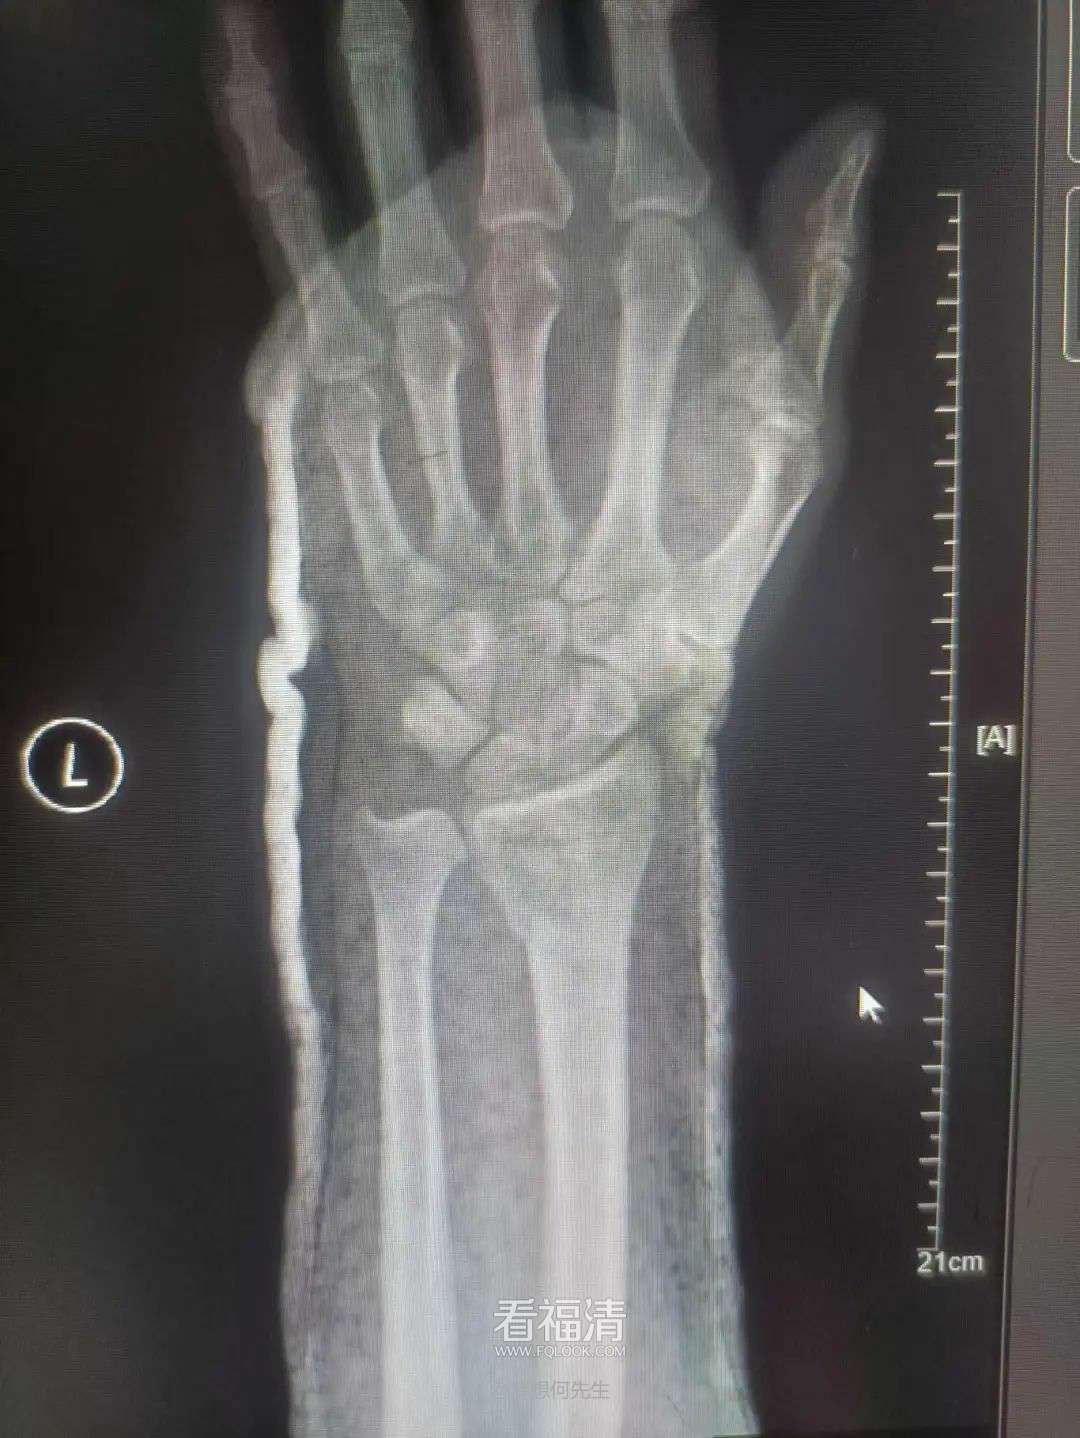

患者39岁,因外伤导致左手疼痛难忍,前来福清市第五医院中医骨科门诊寻求治疗。经过详细检查,患者被确诊为左侧桡骨远端粉碎性骨折伴下尺桡关节脱位。接诊的王征勇运用精湛的正骨手法进行复位,并在中医正骨理论的指导下,使用石膏进行固定。这种治疗方案有效地稳定了复位后的桡骨远端骨折,促进了骨折的愈合,避免了不必要的手术治疗,同时显著减轻了患者的疼痛感。

复位前